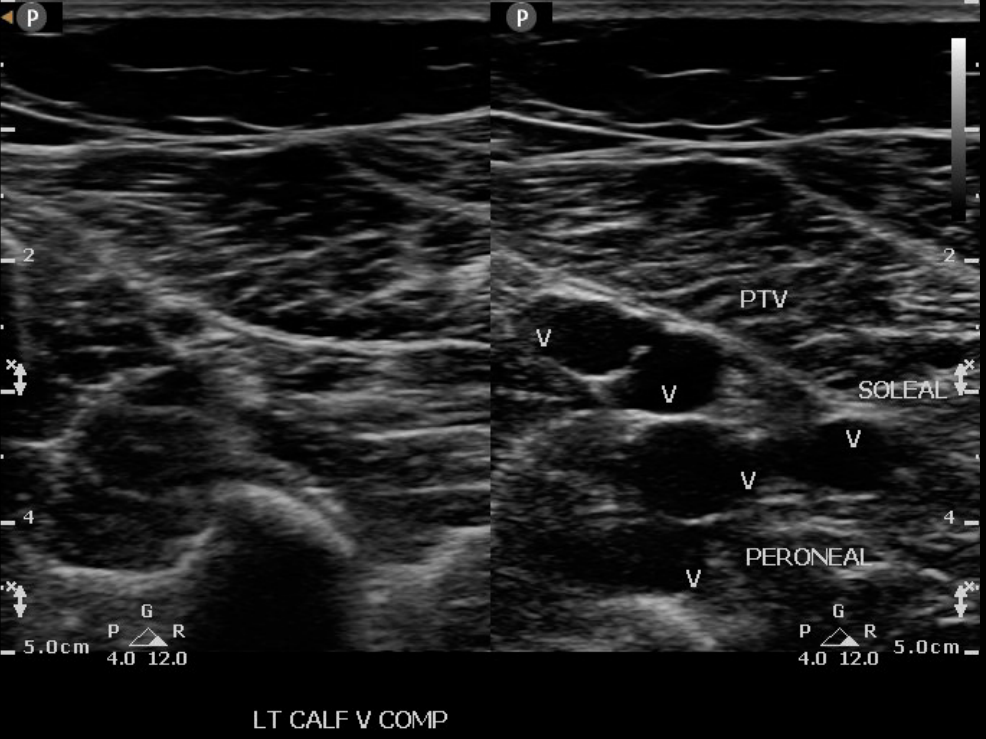

Deep Vein Thrombosis RCEMLearning Soleus Muscle Dvt soleus muscle injuries can be acute or chronic and are usually considered to be a minor discomfort by both the patient and the sports. the majority of lower extremity dvts develop in the veins of the calf, namely the peroneal veins, posterior tibial veins and the veins of the. the soleal vein is a deep vein in. Soleus Muscle Dvt.

Venous Ultrasound HandsOn Training Vascular HandsOn Education RVS Soleus Muscle Dvt the majority of lower extremity dvts develop in the veins of the calf, namely the peroneal veins, posterior tibial veins and the veins of the. the 2012 american college of chest physicians guidelines 5 divided deep venous thrombosis (dvt) into either proximal or. soleus muscle injuries can be acute or chronic and are usually considered to be. Soleus Muscle Dvt.